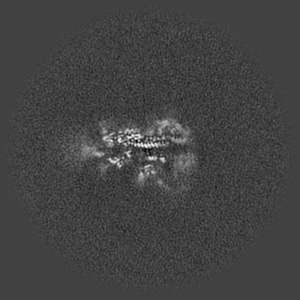

Cryo-EM map of NTD-directed neutralizing antibody 1-68 in complex with prefusion SARS-CoV-2 spike glycoprotein

Single-particle3.8 Å

Sample: Prefusion SARS-CoV-2 spike glycoprotein in complex with 1-68 Fab